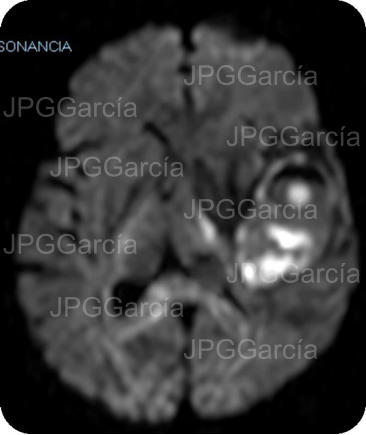

Secuencia de resonancia craneal DW1 y STIR que muestran diferentes intensidades dentro de la lesión descrita que ejerce efecto de vector contra estructuras cerebrales